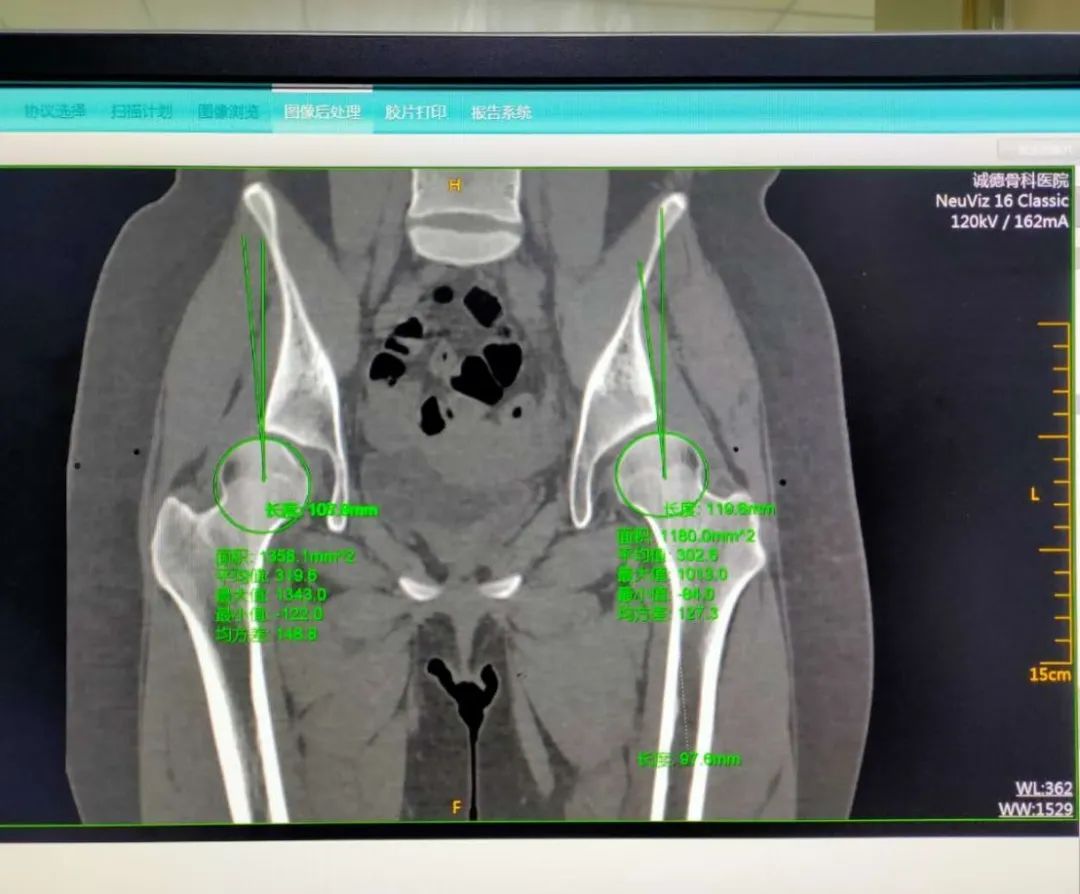

今年15歲的孫某,出現(xiàn)雙側(cè)髖部疼痛,呈持續(xù)性隱痛,只采取口服藥物的保守治療,但是疼痛未見減輕反而愈演愈烈,于是到誠德骨科醫(yī)院集團(tuán)(市中院區(qū))尋求專家的幫助,經(jīng)過多方檢查和論證后,劉德俊院長診斷為:

先天性多發(fā)性骨骺發(fā)育不良,并決定為其實施“髖臼周圍截骨術(shù)”。

據(jù)了解,髖關(guān)節(jié)發(fā)育不良是引起繼發(fā)性髖關(guān)節(jié)炎的重要致病因素之一,髖臼周圍截骨術(shù)能夠有效改善髖臼覆蓋、增加負(fù)重關(guān)節(jié)面,內(nèi)移髖關(guān)節(jié)的旋轉(zhuǎn)中心,從而減小髖關(guān)節(jié)負(fù)重面軟骨應(yīng)力,達(dá)到預(yù)防和推遲骨關(guān)節(jié)炎發(fā)生的目的。